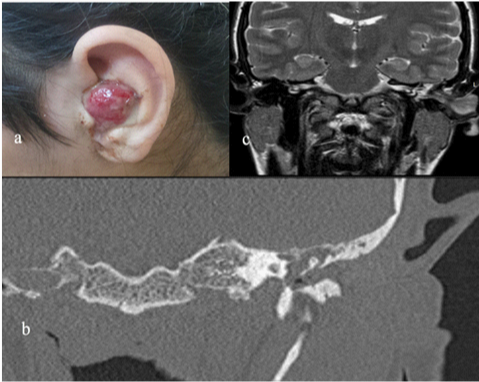

A 19 year-old female patient with mild mental retardation was referred to our clinic due to a red, pulsatile and painful lesion located in the left ear (Figure 1A). She had been treated with the ciprofloxacin drops for the chronic otitis media and there was no history of trauma, pregnancy or facial nerve dysfunction. On the pure tone audiometer right ear: 10 dB, left ear: 75 dB (severe conductive hearing loss) detected. Temporal bone Computerized Tomography (CT) images showed that the soft tissue was located in the left ear canal and no bone defect was detected (Figure 1B). Magnetic resonance imaging (MRI) revealed a 30x20x10mm vascular external ear canal mass (Figure 1C). Digital subtraction angiography (DSA) showed a lesion with delayed contrast retention, reminiscent of a hemangioma (Figure 2). Patient underwent canal wall down mastoidectomy operation and a hemangioma originating from the inferior external ear canal was excised with clean surgical margins. Early and delayed postoperative course was uneventful.

Figure 1 (A) External auditory canal placed lesion on left ear. (B) Coronal computed tomography of the left temporal bone, showing the soft tissue density on the external auditory canal. There is no evidence of the bone destruction. (C) Coronal of the T2-weighted magnetic resonance images of the left temporal bone, showing the high intensity of the pedinculated soft tissue placed on the external auditory canal.